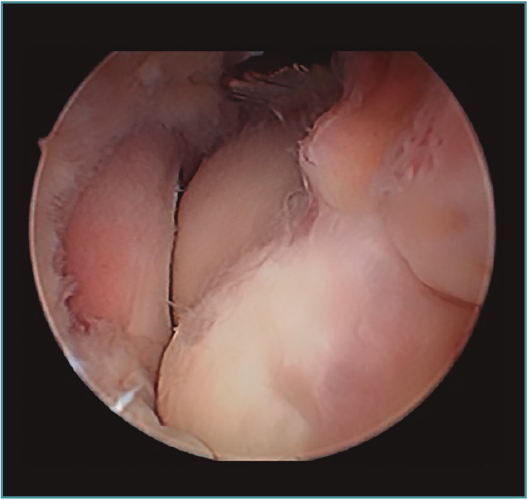

Acto seguido, realizamos nuestra secuencia de trabajo descrita anteriormente (visualización, creación de espacio, trabajo óseo y trabajo de partes blandas). El fresado óseo debe realizarse siempre con el instrumental motorizado orientado hacia el húmero, para evitar las lesiones de partes blandas. El uso de fresas o el sinoviotomo en modo no oscilante y a alta velocidad nos permitirá eliminar los osteofitos que interfieran con la movilidad, especialmente aquellos que ocupan la fosa radial o coronoidea (Figura 8). También es frecuente tener que eliminar osteofitos que aumentan la altura de la coronoides (Figura 9). Una vez eliminado el material óseo (Figura 10), flexionamos el codo para comprobar el aumento de flexión conseguido, que no será completo hasta que liberemos la cápsula posterior y la banda posterior del ligamento colateral medial. Como último paso en la cámara anterior, procedemos a la eliminación de la cápsula articular. Introducimos un Basket recto desde el portal anteromedial y vamos mordiendo la cápsula, atrapándola, cortándola y realizando un movimiento de batido hacia proximal para separar el fragmento capsular de las partes blandas anteriores. Progresamos lateralmente, descubriendo el vientre muscular del braquial anterior, hasta que aparezca tejido graso detrás de la cápsula resecada. En este momento, cambiamos los portales y miramos desde el portal anteromedial proximal y utilizamos la pinza Basket desde el portal anterolateral. Una vez realizada esta capsulotomía amplia, usamos el sinoviotomo para eliminar los restos capsulares proximales. Durante todo este proceso, utilizamos un retractor desde el portal anterolateral proximal para tensar la cápsula y proteger, sobre todo, el nervio radial, que queda situado justo en la grasa lateral al músculo braquial y anterior a la cabeza del radio, y a escasos milímetros de nuestro instrumental de trabajo; aunque no es aconsejable, es posible traccionar de él e introducirlo en la articulación con ayuda de un palpador introducido en la grasa que lo recubre. El nervio mediano se encuentra medial al músculo braquial, pero en un plano bastante más anterior, lo cual hace que esté mucho más protegido(12,13).

Figura 8. Osteofitos ocupando la fosa radial y coronoidea, observados desde el portal anteromedial proximal.

Figura 9. Osteofito coronoideo observado desde el portal anterolateral.

Figura 10. Mismo caso que en las Figuras 8 y 9 después del trabajo óseo. Obsérvese la recreación y fusión de ambas fosas radial y coronoidea con el típico aspecto de “tobogán” después del fresado de la cara anterior del húmero y la disminución de la altura de la coronoides. Todavía no se ha procedido a realizar la capsulectomía.